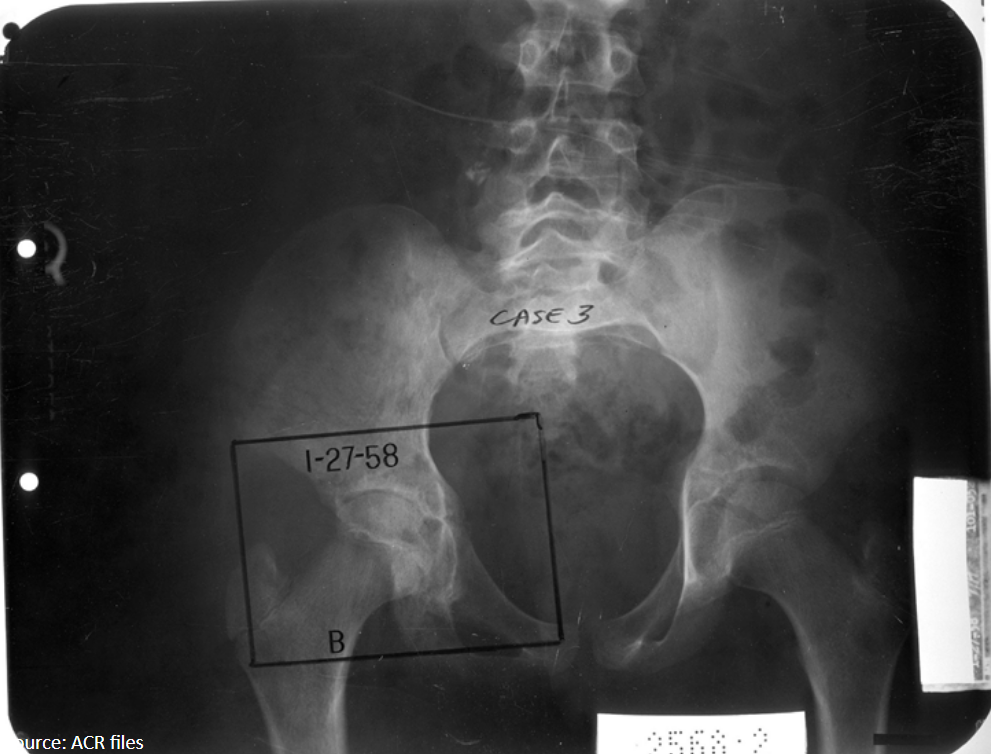

11

Q

What radiographic sign is present?

What does this mean by definition?

A

Waldenstrom’s sign: uneven hip joint space (one is increased) due to joint capsule swelling laterally displacing the femur

AVN of femoral capital epiphysis: LCP

12

12-year-old female presents with hip pain that refers to the knee.

Based on the evidence of avascular necrosis in her femoral capital epiphysis, what is the diagnosis?

Legg-Calve-Perthes (LCP)

Waldenstrom sign present

13

10-year-old female presents with a painful limp.

What is the diagnosis?

LCP

Legg-Calve-Perthes

sclerosis and flattening with epiphyseal fragmentation of femur (AVN)

14

What findings are seen in the right femur?

Mushroom deformity, degenerative changes, superolateral displacement of femoral head